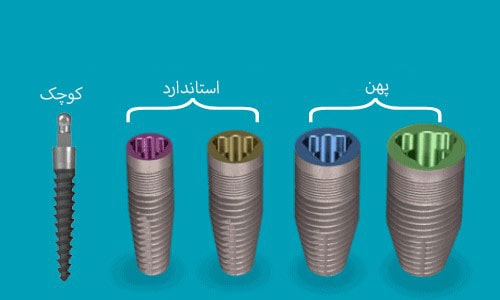

اندازه ایمپلنت

گروه بندی دیگر ایمپلنت ها بر اساس سایز آنها (که سطح نیز نامیده می شود) می باشد و بیانگر این است که به طور کلی در کجای دهان می توانند قرار بگیرند. با این حال، هر موردی متفاوت می باشد، فضای منحصر به فرد و نیاز استخوانی در دسترس، اندازه ایمپلنت را مشخص می کند. پایه ایمپلنت، قطر و ارتفاع دارد که هر دو برای انتخاب آن مهم می باشند.

سطح استاندارد

ایمپلنت های دندانی استاندارد از سایز 3.5 تا 4.2 میلی متر قطر دارند. ایمپلنت های نسبتاً کوتاه تر و نازکتر معمولاً در جلوی دهان استفاده می شوند.

سطح بزرگ

اندازه قطر ایمپلنت های دندانی بزرگ از 4.5 تا 6 میلی متر می باشند و عمدتاً در عقب دهان کاربرد دارند.

ایمپلنت های نازک یا مینی: ایمپلنت های کوچک از 2 تا 3.5 میلی متر قطر دارند و معمولاً برای بیمارانی که فضای کافی بین ریشه های دندان ندارند قرار می گیرند. ممکن است زمانی که بیمار تراکم استخوانی پایینی نیز داشته باشد از این ایمپلنت ها استفاده شود. گاهی برای پشتیبانی موقت پروتزهای موقتی نیز استفاده می شود، اما ایمپلنت های دائمی با استخوان ادغام می شوند.